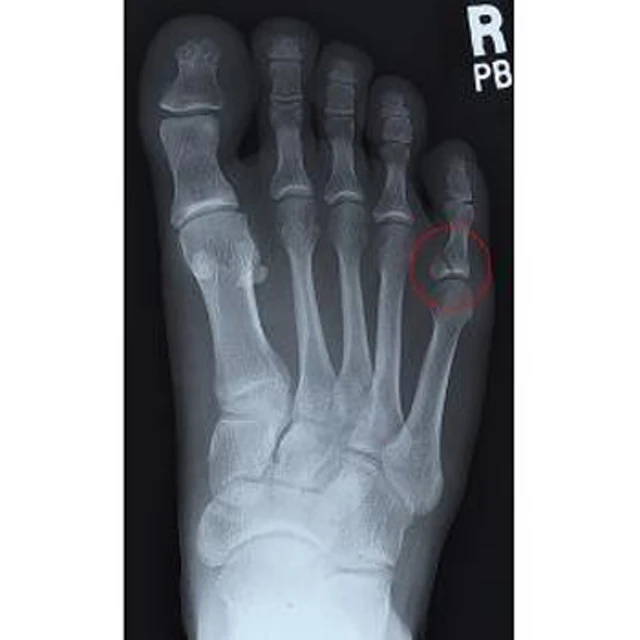

Диафиз фаланги пальца

Диафиз фаланги пальца 108 фотографий